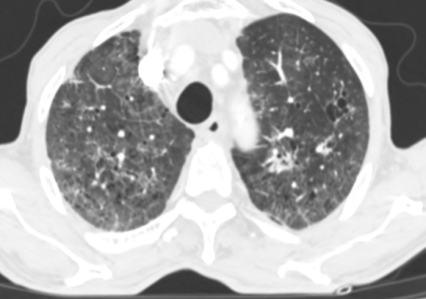

在接下来的救治过程中,挑战接踵而至。患者相继出现了血痰、血便、顽固性的低钠血症和心脏早搏等问题,治疗团队如同闯关一般,对每一个新情况都及时研判并调整用药策略。随着治疗的深入,患者的体温首先恢复正常,成为病情好转的曙光。之后的复查CT显示,肺部炎症开始逐步吸收。虽然过程中出现了肺纤维化的迹象,但通过加用抗纤维化药物尼达尼布,这一进程也得到了有效干预。

在呼吸与危重症医学科全体医护人员日以继夜的精心照护下,患者的康复之路渐渐清晰。他从完全依赖高流量吸氧,到可以尝试在床旁活动;从需要全程卧床,到能够借助鼻导管吸氧下床如厕。最终,在入院41天后,王大爷成功脱氧,能够自主缓慢行走,基本恢复了生活自理能力,顺利出院。